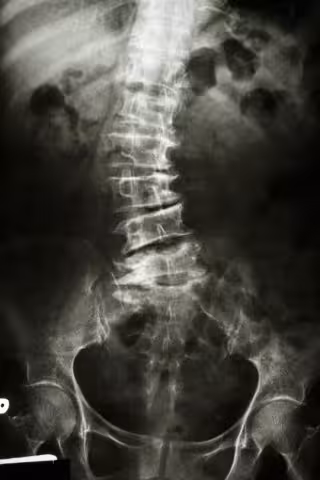

Escoliosis, radiografia, espalada

La escoliosis es una desviación de la columna vertebral que da lugar a una curvatura anómala; el tipo más común es la escoliosis idiopática, o de origen desconocido, aunque se sabe que puede ser un problema común en una misma familia.